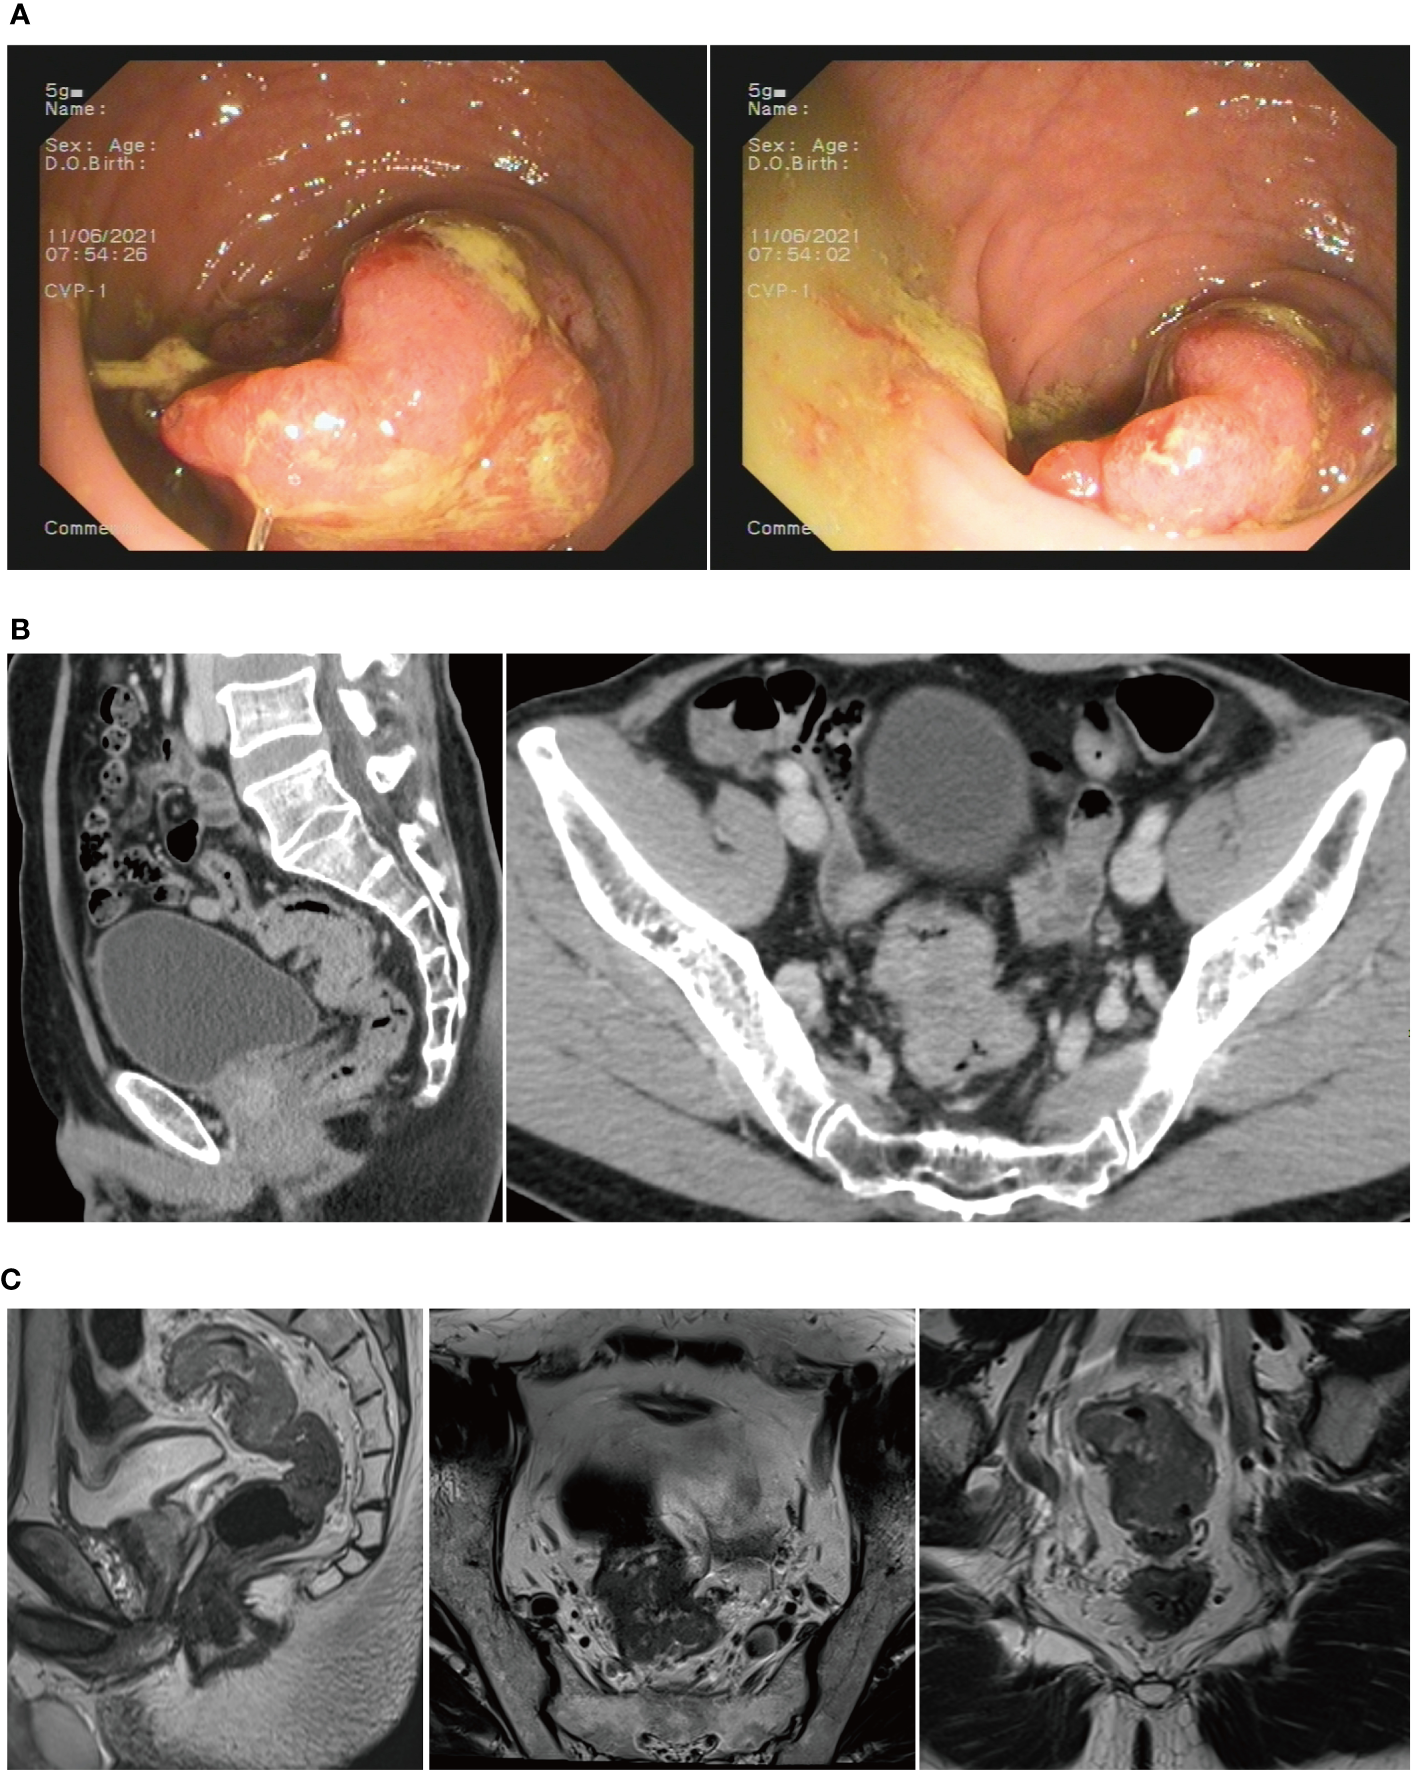

The patient was admitted to the First Hospital of Chongqing Medical University with the chief complaint of “change in stool habit for 5 months.” The rectal finger examination did not reveal a mass, but the retracted finger was stained with blood. The colonoscopy on June 11, 2021, suggested the presence of a rectal cauliflower-like neoplasm at 11 cm from the anal verge, with surface erosion and bleeding, invading most of the intestinal lumen so that it was narrowed, only allowing the colonoscope to barely pass through (Figure 2A). Pathological examination after colonoscopy suggested adenocarcinoma. Enhanced CT on June 13, 2021, suggested an uneven eccentric thickening of the rectal wall with the plasma membrane surface rough, which was considered as a tumor-like lesion with a high possibility of rectal cancer. The lesion was surrounded by multiple small lymph nodes in the superior rectal artery (Figure 2B). Moreover, the pelvic MRI suggested rectal cancer at 11.0 cm from the anal verge, with the MR stage at T4aN1, circumferential resection margin (CRM) (+), extramural venous invasion (EMVI) (−), and enlarged lymph nodes behind the left seminal vesicle (Figure 2C). The CA19–9 was 89.9 kU/L. The patient was diagnosed with upper rectal cancer.

Figure 2

(A) Colonoscopy revealed a rectal cauliflower-like neoplasm. (B) CT scans showed a tumor-like lesion in the rectum. (C) MRI suggested rectal cancer.